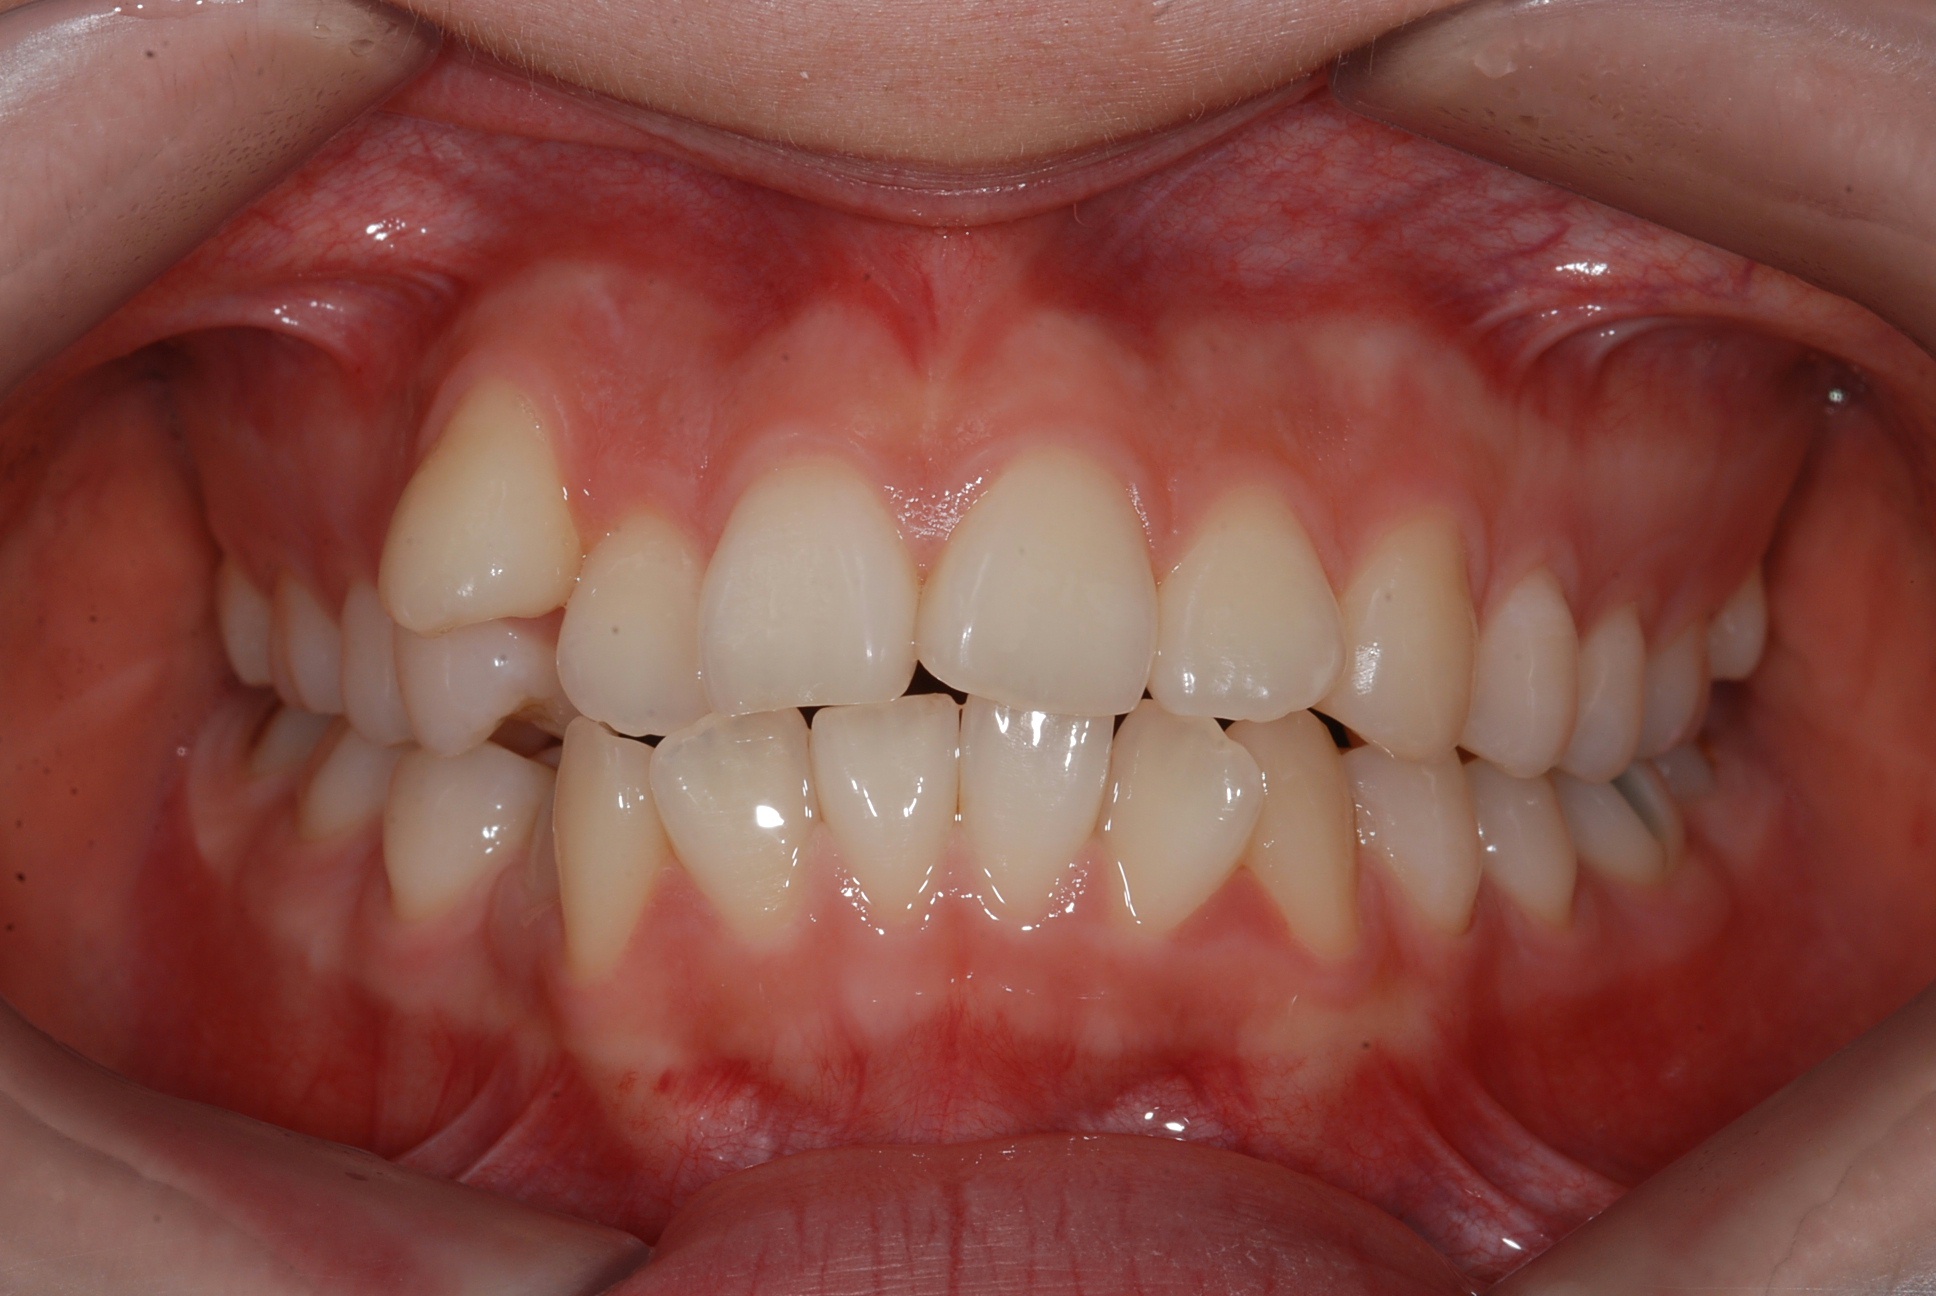

치료 전 사진입니다.